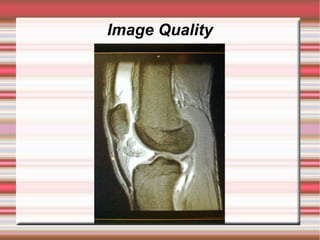

   Good coil position

has given this image

nice even signal over

the area of interest